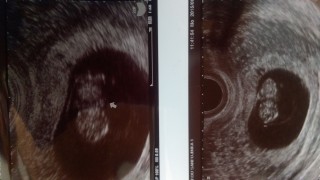

切迫流産で2週間入院し退院5日後のわが子。頭殿長が2.58cmの平均的で順調な成長だそうです。流産の二文字が頭から消えず、オロオロしている間に赤ちゃんはがんばって生きていてくれたんだと思うと、もっとしっかり守っていかなきゃと改めて感じました。このエコー写真、ダンナさんはすでに待ち受け画面にしてますw

9w5d。 毎回の診察でドキドキ。 心配とは裏腹に元気に動く心臓に、いつも涙が溢れてきます。 切迫流産で入院中ですが、出血もおさまり、週末退院予定。 今回の写真ドキンちゃんにみえると母に言われ、より一層愛おしく 可愛さ倍増♡これからもすくすく育ってね。